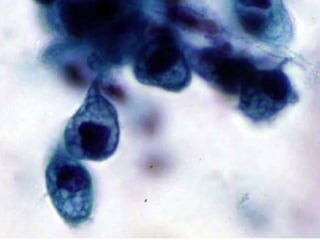

Benign cellularBenign cellular

proliferationsproliferations

• Creola body

– Bronchial cell hyperplasia

• Goblet cell hyperplasia

– Mucin vacuoles with small nuclei

• Reserved cell

– Basal cells with molded nuclei

Benign cellularBenign cellular proliferationsproliferations •Creola body – Bronchial cell hyperplasia • Goblet cell hyperplasia – Mucin vacuoles with small nuclei • Reserved cell – Basal cells with molded nuclei